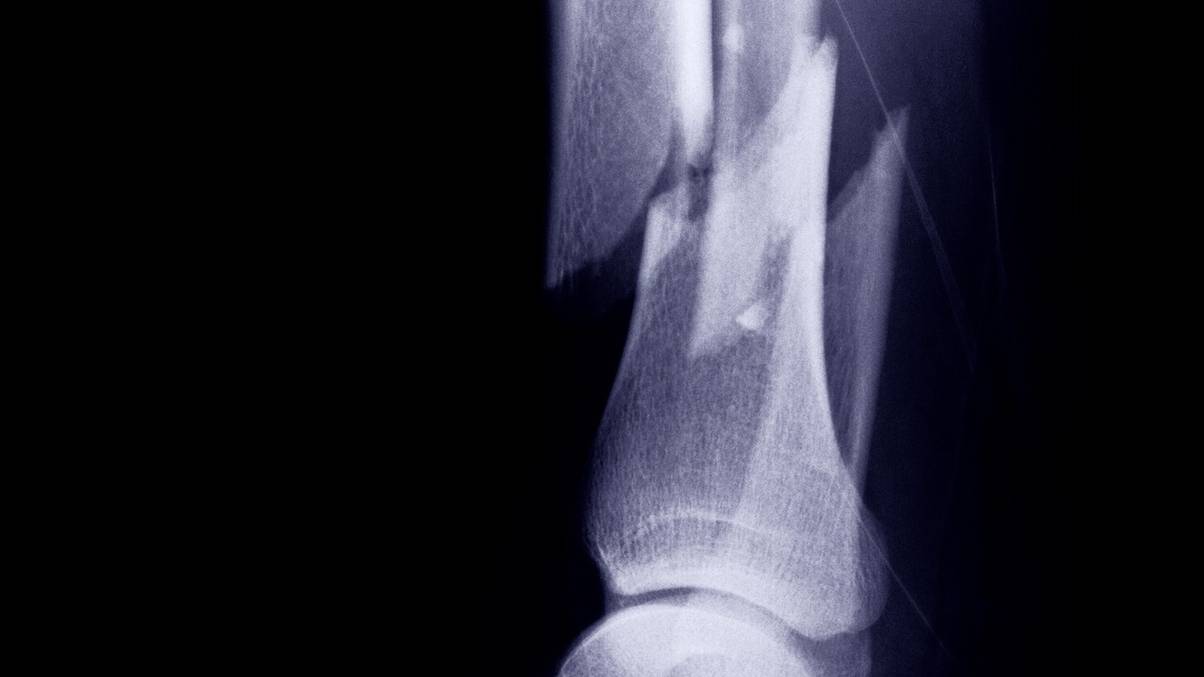

There may be presently no scientific proof to again the idea up, and research have really even pointed in the direction of the alternative being true. A 2015 paper showed that these experiencing hardship or psychological well being points may very well have worse bone well being, as youngsters with fractured bones are often in poorer households. The damaged bones have been almost certainly brought on by falls, blunt trauma, or street accidents, and are often present in youngsters who expertise abuse.

These with main depressive dysfunction (MDD) have been additionally discovered to be extra prone to getting osteoporosis, a well being situation which weakens bones and subsequently will increase the probability of fractures, in accordance to a 2021 examine.

Individuals with excessive BMD can nonetheless endure damaged bones, with a decrease density merely elevating the probability of fractures.